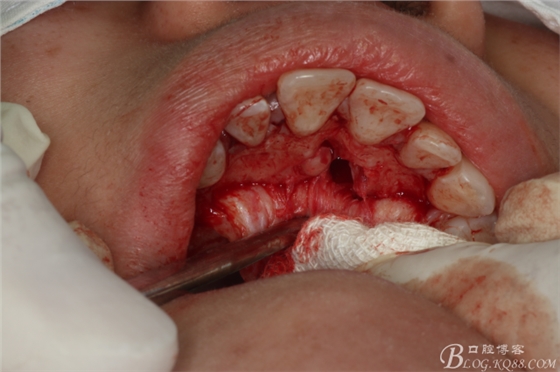

圖12.取出左邊上頜多生牙后,鼻腭管擴(kuò)大了,鼻腭神經(jīng)人那個(gè)腭側(cè)粘膜相連未斷。

圖13.去骨、暴露11腭側(cè)部分多生牙